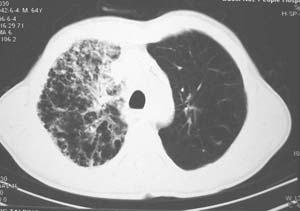

右肺上叶见片状 网格状及索条致密影.其内参杂斑点状小结节,部分融合,密度不均匀,内见含气支气管像,纵隔内见肿大淋巴结,其他肺呈代偿性肺气肿像.结合男 64  咳血,咳痰 发热 3天 血象1.2万,综合考虑:1 慢性炎症伴间质纤维化 肺气肿.2 不除外特发性感染的可能.

右肺上叶大片片状、网格状及索条致密影,前半部密实向后逐渐疏松,其内参杂斑点状小结节,密度不均匀,内见含气支气管像,纵隔内见肿大淋巴结,其他肺呈弥漫性小叶中心性性肺气肿改变,结合男 64  咳血,咳痰,发热3天,血象1.2万。考虑:1 慢性支气管炎、肺气肿合并右上肺感染。2 不除外结核合并感染的可能。

右肺上叶见片状 网格状及索条致密影.其内参杂斑点状小结节,部分融合,密度不均匀,内见含气支气管像,前段有一小片结影,纵隔内见肿大淋巴结,右侧胸腔少量积液。.结合男 64  咳血,咳痰 发热 3天 血象1.2万,综合考虑:2 右上肺感染伴间质纤维化 2 警惕细支气管肺泡癌。3建议结合临床及进一步检查[痰及纤支镜]或治疗后复查

右侧胸廓略小于左侧,右肺上叶大片实变影,近肺门处密度较高,内见支气管气相,周围较淡,呈网格状,余肺野清晰,纵隔内见肿大淋巴结,右侧胸腔少量积液。临床 咳血,咳痰 发热 , 血象1.2万。

考虑大叶性肺炎。

影像表现:肺窗示右肺上中叶均可见小片、条索状、小结状密度增高影,可见支气管充气相,小叶间隔增厚,支气管通畅,余肺未见明显异常。纵隔窗示4r可见小淋巴结融合,无明显肿大,右侧示少量胸腔积液。

诊断:提示右肺上中叶感染性病变,tb可能大。

右侧胸阔塌陷,纵隔右移。右上肺大片状高密度影,沿支气管血管束走行,内见点状钙化;支气管充气征阳性,支气管呈柱状扩张;胸膜下小叶间隔增厚;右侧后胸壁内侧见带状水样密度影;纵隔淋巴结增大。

考虑:①右上叶陈旧性结核合并感染可能大。②右侧少量胸水。

影像学表现:右肺上叶大片状、网格状及索条致密影,前半部密实向后逐渐疏松,其内参杂斑点状小结节,密度不均匀,内见含气支气管像,纵隔内见肿大淋巴结.

综上,以右上肺tb(干酪性肺炎)首先考虑.当然大叶性肺炎不能除外.(血象不是特别高,纵隔内淋巴结肿大,也不甚支持.).如果经积极抗感染治疗,病灶明显好转.更能明确为大叶性肺炎.也不能明确排除肺ca.建议痰培养和纤支镜.

右肺上叶见片状,网格状及索条样致密影,内见支气管气相,纵隔内见肿大淋巴结,同侧胸腔内少量液性密度影,余肺呈肺气肿改变,临床:男,64岁,咳血,咳痰,发热3天,wbc---1.2万

考虑:1)右肺大叶性肺炎2)肺气肿